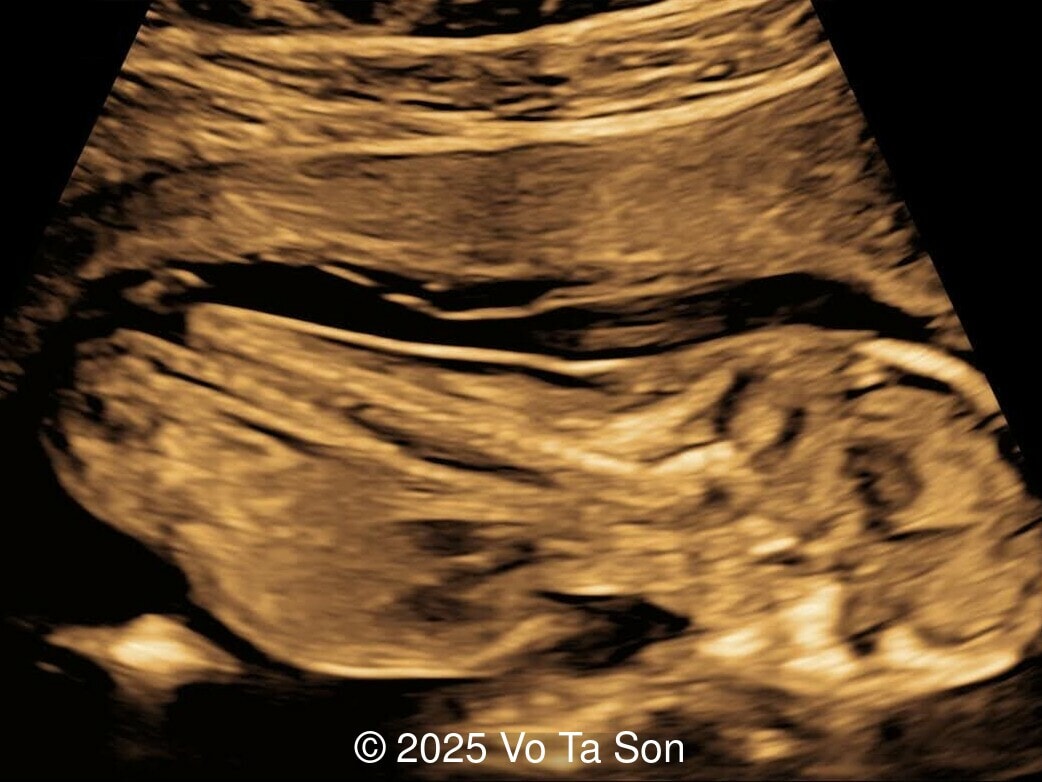

Our imaging revealed the following significant fetal abnormalities:

• Open spina bifida in the sacral region with dry brain sign, crash sign, BS/BSOB >1, and a lesion at the sacral coccygeal spine. The spinal lesion observed in the sacral region is characterized by a posterior vertebral arch defect and a protruding meningeal sac.